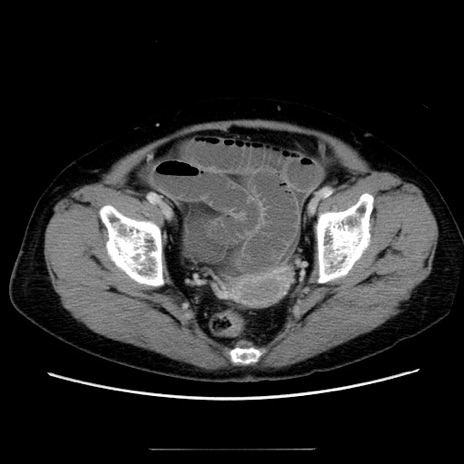

冠状断像

【症例】70歳代女性

【主訴】お腹が張る

【現病歴】1週間くらい前から腹部膨満の自覚あり。昨日夜から増悪したため、本日救急外来受診。

【身体所見】意識清明、BT 36.5℃、BP 165/106mmHg、HR 80bpm、SpO2 98%、腹部:膨満、軟、自発痛・圧痛なし、触診にて不快感あり、腸蠕動音:減弱

【データ】WBC 12600、CRP 1.04